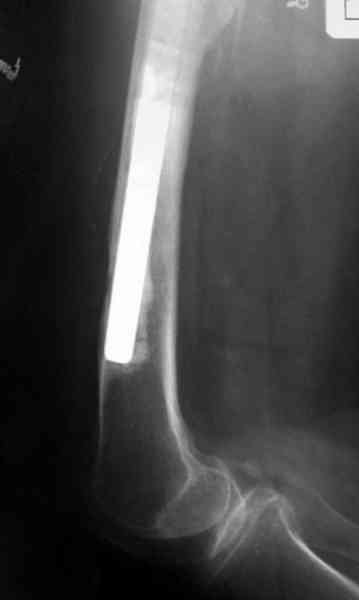

Приготовлен цемент из расчета: Tobramycin 2.4 g (2 флакона), Vancomycin 2 млн (4 флакона) и 2 упаковки цемента с добавлением дополнительного флакона цементной жидкости.

После обработки ацетабулярного компонента, ещё в мягком цементе в полости вертлужной впадины головкой бедренного компонента сделана выемка для головки, чтобы свежий цемент не прилипал к головке. Головку бедренного компонента завернул обычной стерильной фольгой, которую после образования выемки отлепил от головки.

Для спейсера в бедро использовал старый длинный бедренний компонент меньшего диаметра, облепленный со всех сторон цементом с антибиотиком.

Наглухо ушитая рана с дренажом зажила первично, после чего с больной потерял контакт, и только недавно, через 8 лет я осмотрел её. Она без проблем нагружает на конечность и передвигается с помощью трости. От окончательной операции по реконструкции отказывается, довольная результатом.

Имеются литературные данные, когда спейсер держали не более 6 месяцев, но этот случай бьет все рекорды, может быть для наших людей, обременных финансовыми трудностями, нужна другая шкала оценки сроков нахождения спейсеров.